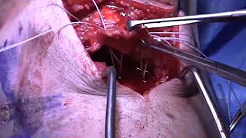

Chronic Patellar Tendon Reconstruction after Failure